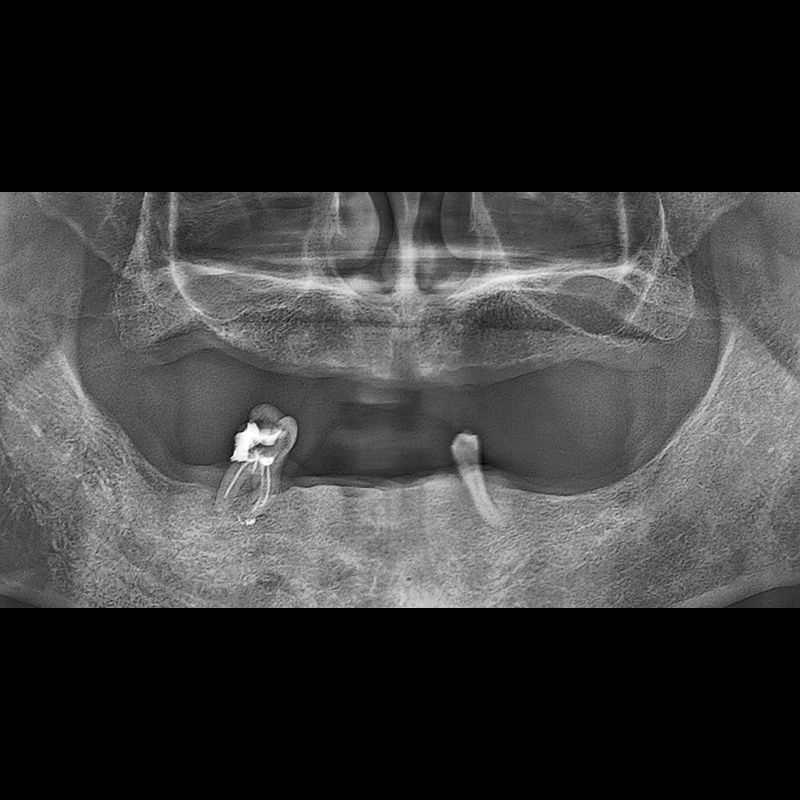

BEFORE AFTER

임플란트 전후사진 2025.05.30

결손된 치아 부분과 살리기 힘든 치아 위치에 임플란트를 식립하였습니다.